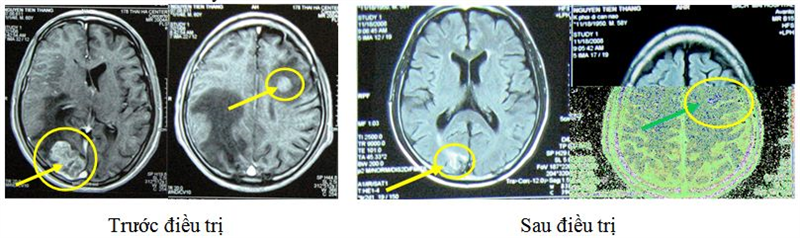

Bệnh nhân Nguyễn Văn Th, nam, 50 tuổi,

Chấn đoán: Ung thư phổi di căn não

Chỉ định: RGK liều 18Gy

Hình ảnh trước và sau điều trị 6 tháng. Trước điều trị: tổn thương não 2 ổ kích thước 3x4cm, 1x2 cm, phù não rộng. Bệnh nhân đau đầu nhiều. Sau điều trị 6 tháng: tổn thương gần như không còn, hết phù não.

Bệnh nhân Nguyễn Thị Hồng L, nữ, 54 tuổi

Chẩn đoán: NH Lymphoma đã điều trị hóa chất 6 đợt, xạ gia tốc 60Gy

Chỉ định: RGK liều 14 Gy

Trước điều trị, bệnh nhân đau đầu nhiều, kích thước u: 2x3 cm, bệnh nhân đã được điều trị hóa chất 6 đợt, xạ gia tốc 60Gy. Sau xạ phẫu RGK liều 14 Gy, lâm sàng cải thiện, giảm đau đầu, tổn thương gần như biến mất.